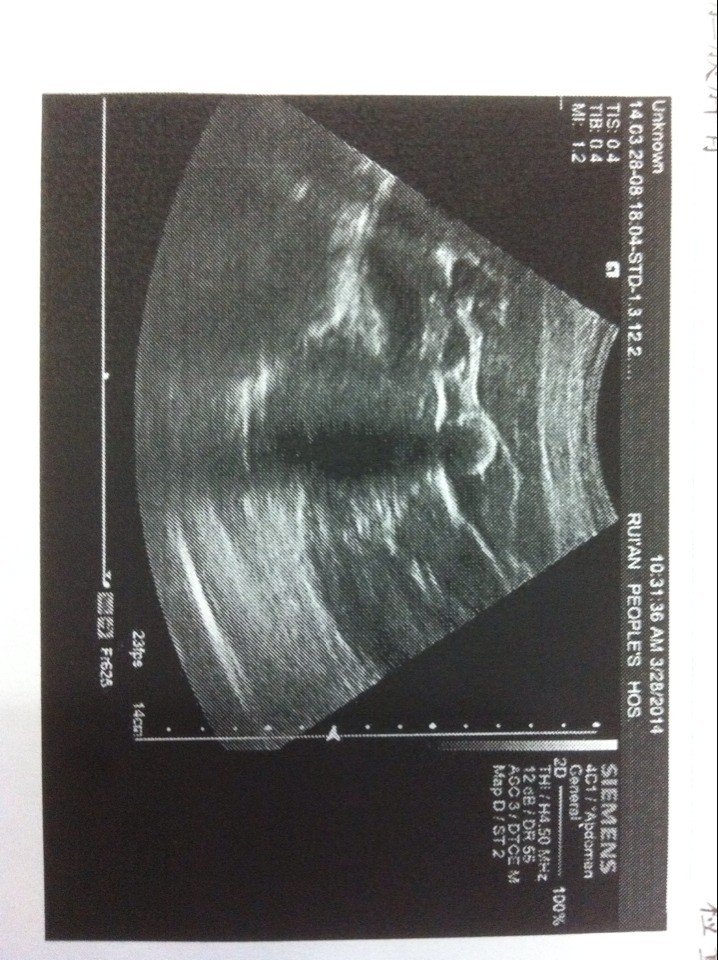

被查有胆结石 没什么感觉怎么处理好!28岁还想生小孩子 是做了再要孩子还是不用做可以要孩子 。 点击展开 匿名用户 2014-03-29 17:28 为您推荐: 其他回答 病情分析: 你好,根据你说的情况,没什么症状,不要担心的,可以要孩子的。 指导意见: 胆囊结石只有手术治疗,现在腹腔镜手术创伤也是很小的,根据的具体情况选择是否治疗,对要孩子没什么影响的,祝身体健康。 匿名用户 2014-03-29 21:33 相关问题 一岁零4个月的小孩子得了流沙性胆结石该怎么办? 婴儿和小孩子吃含三聚氰胺的奶粉会造成胆结石吗?